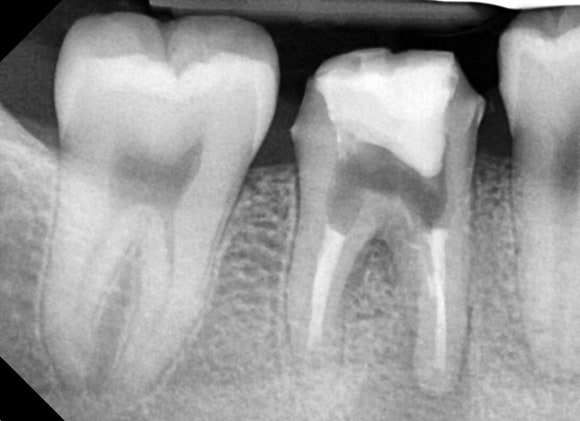

20250528

치료 종료 후 3개월에

경과 관찰을 위해 촬영한 사진입니다.

치아 뿌리 끝에 매달려 있던

검은 염증 주머니가 거의 다 사라진 것을

확인할 수 있습니다.